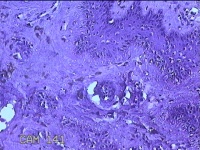

左侧臀部结节

性别

女

年龄

24岁

临床诊断

皮下结节

一般病史

发现左侧臀部结节1年余。

标本名称

大体所见

灰白暗红色带皮肤样结节0.7x0.3x0.2cm一个,表面糜烂,切开结节呈实性,切面灰白暗红色,质软。

图1